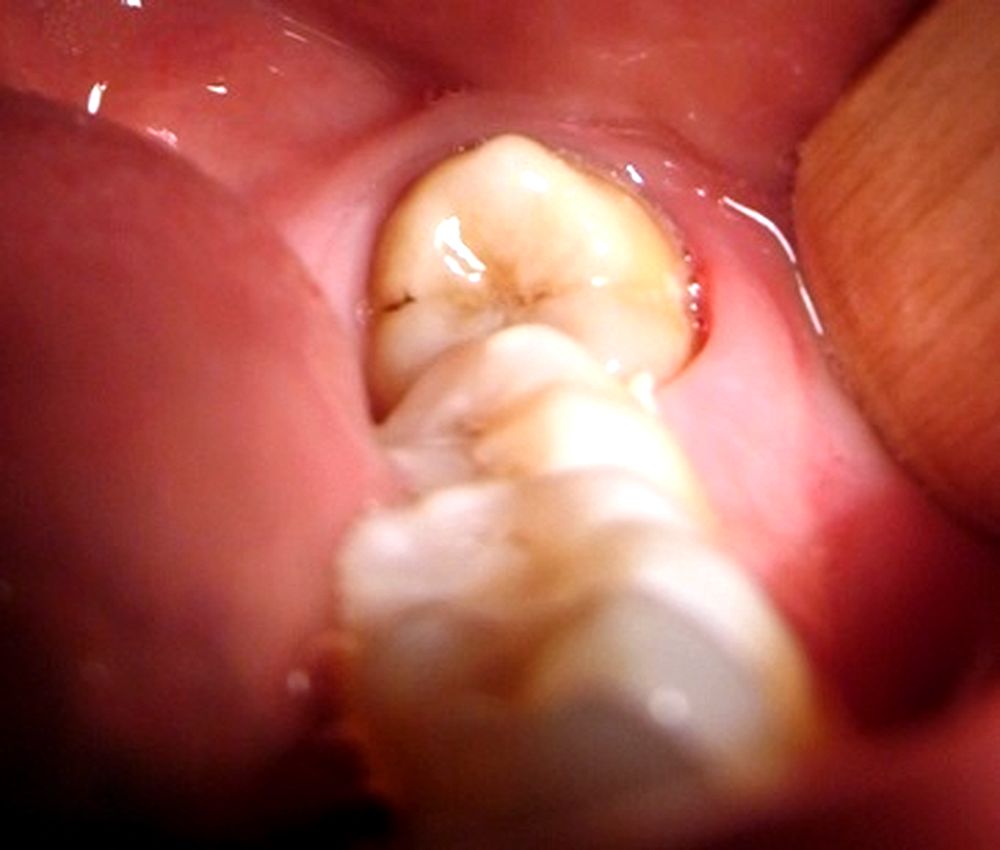

Las muelas de juicio, o terceros molares, son los dientes permanentes de la boca que salen últimos. Estas muelas suelen salir entre los 17 y los 25 años de edad. A algunas personas nunca les salen las muelas de juicio. En otros, las muelas de juicio salen normalmente, al igual que las otras muelas, y no causan problemas.. Edad de aparición de las muelas del juicio. El intervalo de edad en el que suelen aparecer las muelas del juicio es entre los 17 y los 21 años. Durante este período, los terceros molares comienzan a emerger en la parte posterior de la boca. Sin embargo, es importante destacar que la erupción de las muelas del juicio puede ocurrir tanto.